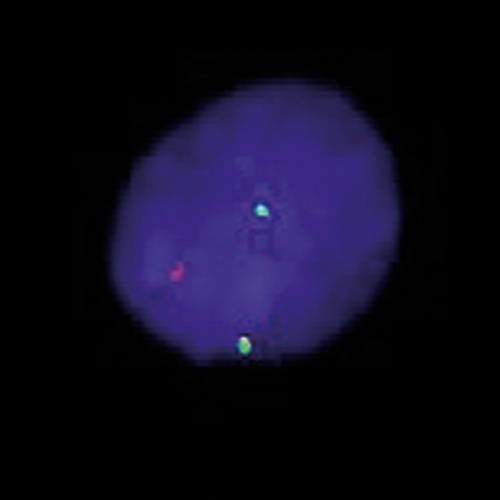

ETV6 (12p13) Break probe hybridized to patient material showing a translocation involving the ETV6 region at 12p13 (1RG1R1G). Image kindly provided by Magret Ratjen, Kiel.

ETV6 (previously known as TEL) gene is the abbreviation for -ETS variant 6- gene. It encodes an ETS family factor which functions as a transcriptional repressor in hematopoiesis and in vascular development. The gene is located on chromosome 12p13, and is frequently rearranged in human leukemias of myeloid or lymphoid origins. Also, systematic deletion of the normal ETV6 allele in patients with ETV6-RUNX1 fusions can be found. The ETV6 Break FISH probe is optimized to detect translocations involving the ETV6 region at 12p13 in a dual-color, split assay on metaphase/interphase spreads and bone marrow cells.